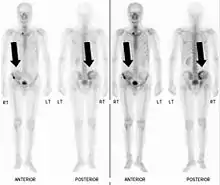

Also known as a bone scan, bone scintigraphy involves the injection of a small amount of radioactive tracer into the bloodstream. This tracer decays and emits radioactive energy which can be detected by a special camera. The camera produces a black and white image where areas shown as dark black indicate bone damage of some kind. If there is a black spot in the lumbar vertebrae (e.g. L5) this indicates damage and potentially spondylolysis. If this test is positive, a CT scan is usually ordered to confirm spondylolysis.[13]

Commonly known as a CT Scan or CAT scan, this form of imaging is very similar to x-ray technology but produces many more images than an x-ray does. The multiple images produce cross-sectional views not possible with an x-ray. This allows a physician or radiologist to examine the images from many more angles than an x-ray allows. For this reason the CT scan is much more accurate in detecting spondylolysis than an x-ray. Bone scintigraphy combined with CT scan is considered the gold standard which means that it is best at detecting spondylolysis.[13][15]